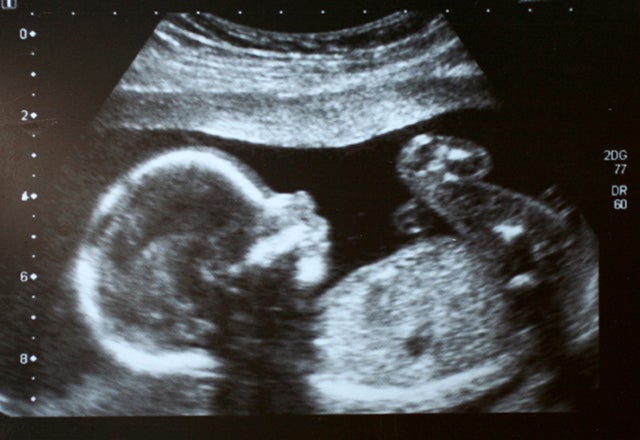

Sadly, unlike my friend going through a mammogram scare, many pregnant women today having prenatal screenings aren’t going through the full battery of tests to see if the “something” they are worried about – most often Down Syndrome or abnormalities that could cause the baby’s death shortly after birth – is actually reality.

According to a recent story by the New England Center for Investigative Reporting, prenatal testing is not nearly as accurate as many believe:

Two recent industry-funded studies show that test results indicating a fetus is at high risk for a chromosomal condition can be a false alarm half of the time. And the rate of false alarms goes up the more rare the condition.

That’s right, a positive test in a prenatal screening is by no means a certainty that the unborn baby has any genetic abnormalities.